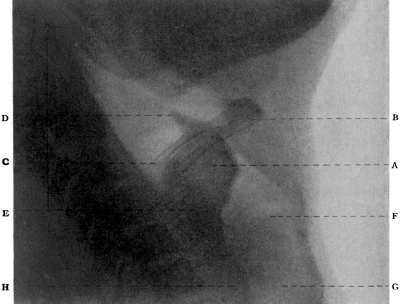

| 334. | Radiograph to show the Value of the Röntgen Rays | 639 |

| 335. | Radiograph showing Canula in the Frontal Sinus | 639 |